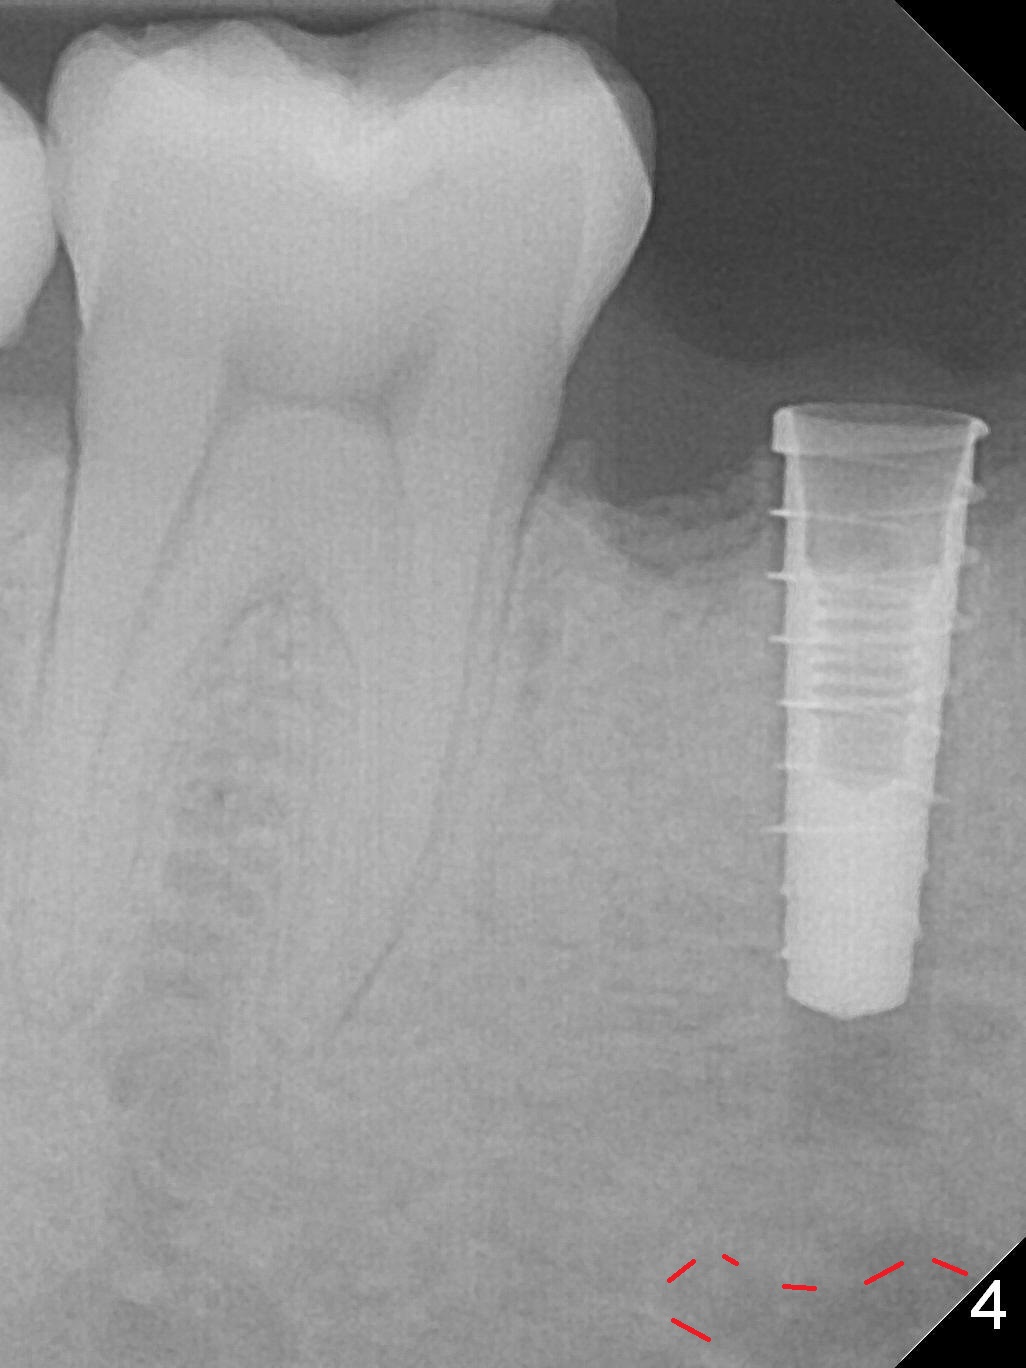

The lower 2nd primary molar has buccal furca lesion (Fig.1 *) with the thin buccal plate (Fig.2). Osteotomy is initiated in the sloped septum (Fig.3). After use of Magic Drill (MD) 3.3 mm for 13 mm and MD 3.8 mm for 11 mm, placement of a 4x11 mm IBS implant meets resistance because of the dense bone (Fig.4-6, red dashed line: Mental Loop) with final insertion torque >50 Ncm. After placement of a 6x4(3) mm abutment and autogenous bone in the remaining shallow sockets (Fig.6), a provisional is fabricated (Fig.7). Finally periodontal dressing is applied. Impression is taken 3 months postop (Fig.8). Buccal infection develops 2 weeks post cementation (Fig.9). When the crown/abutment is removed, there is no residual cement. The implant threads can be felt through the fistula. After soft tissue debridement and copious irrigation, Arestin is placed in the fistula. The latter disappears 15 days post debridement. The patient feels better and moves out of state. It appears that early periimplantitis develops because of the preexisting buccal furca lesion and failure to place the implant deep. The implant will be placed deep after loosening a little (since there is apical space (Fig.8 white line)) or removed, truncated at the apex and placed lower than the buccal crest.